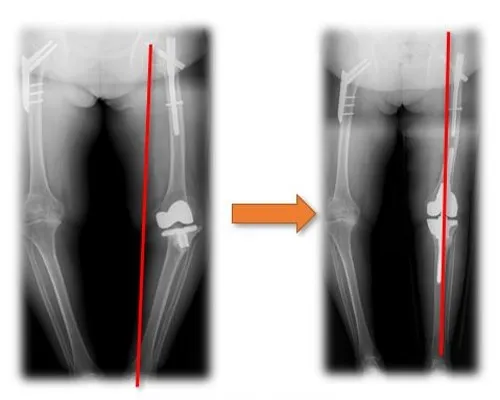

Through three-dimensional reconstruction of medical CT data, porous implants with bionic trabecular structures such as joint, spine, craniofacial bone and extremities can be manufactured by using advanced three-dimensional printing techniques like electron beam melting and selective laser melting. Factors such as porosity and pore size can be adjusted for individuals, which is more conducive to bone growth and clinical effect.